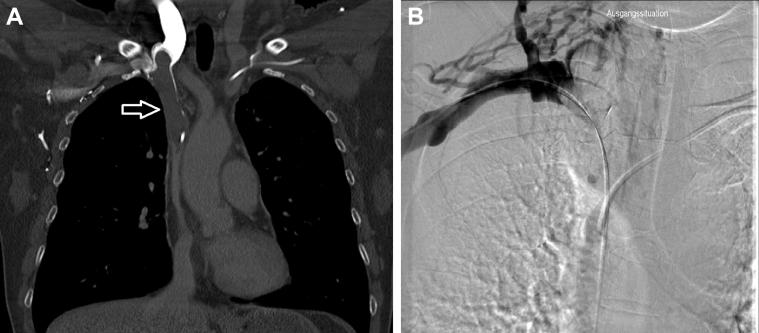

Acute superior vena cava (SVC) syndrome is managed by endovascular recanalization, venoplasty with stenting, and anticoagulation. It is often associated with central venous catheters. We present a case of a 55-year-old woman with acute SVC syndrome due to port-a-cath-associated thrombosis of the SVC and the brachiocephalic and subclavian veins who was treated with catheter-based thrombectomy and local spray thrombolysis, venoplasty, and stent placement. Port-a-cath restoration was achieved in the same session by endovascular snaring and repositioning. This case demonstrates that reoperation with surgical catheter removal and reinsertion of central venous catheters with possible complications (eg, rethrombosis, bleeding) can be avoided by single-session endovascular management.

急性上腔静脉(SVC)综合征的治疗方法包括血管内再通、带支架的静脉成形术和抗凝治疗。它常与中心静脉导管相关。我们报告一例55岁女性,因植入式静脉输液港相关的SVC、头臂静脉和锁骨下静脉血栓形成导致急性SVC综合征,接受了基于导管的血栓切除术、局部喷射溶栓、静脉成形术和支架置入术治疗。在同一次手术中,通过血管内圈套和重新定位实现了植入式静脉输液港的修复。该病例表明,通过单次血管内治疗可避免再次手术取出外科导管并重新插入中心静脉导管可能出现的并发症(如再血栓形成、出血)。